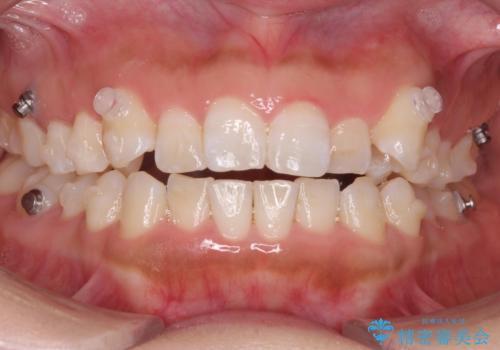

八重歯を非抜歯で マウスピースで治療 奥歯を後ろに下げてすき間を確保

- 八重歯を主訴に来院。

仕事柄ワイヤーが見えるよりはマウスピースで目立たなく歯並びを良くしていきたいとのことでした。

奥歯を後ろに下げてすき間を確保し、八重歯を引っ込めて並べる治療を行いました。

奥歯を後ろに下げるために、矯正用のミニスクリューを使用しています。

かなり真面目に使っていただいた印象で、綺麗に動きました。